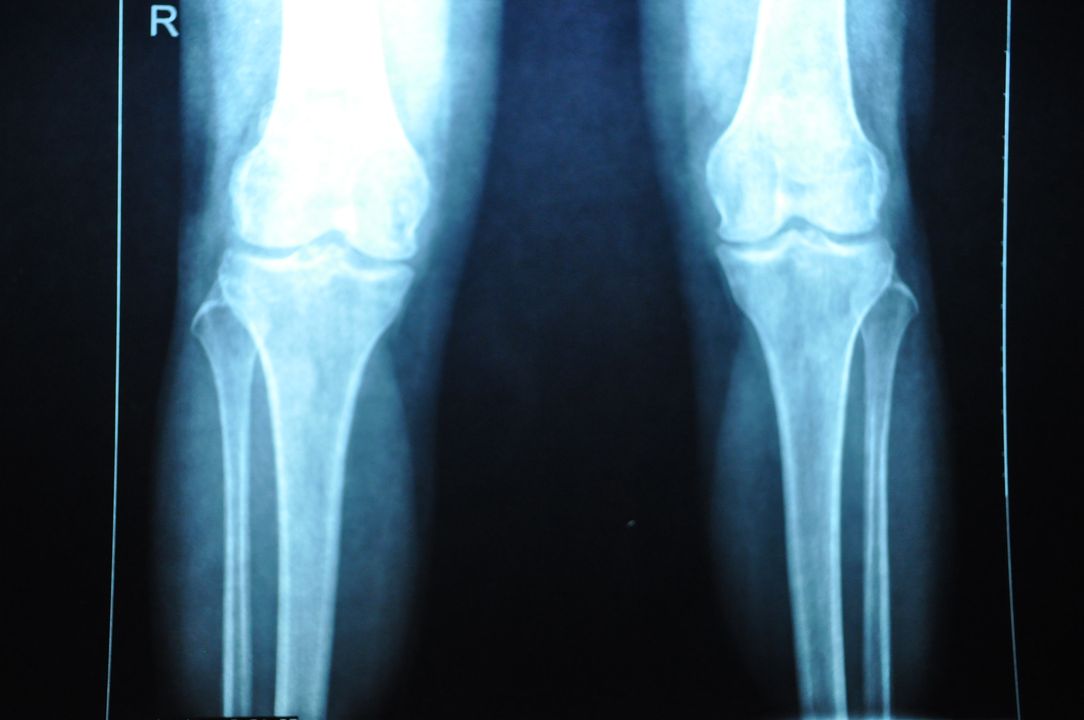

退行性膝关节炎辅助检查

X片检查

实验室检查:1、关节液为非炎性,白细胞一般不超过1000个;2、血沉(ESR)正常;3、抗“O”及类风湿因子阴性